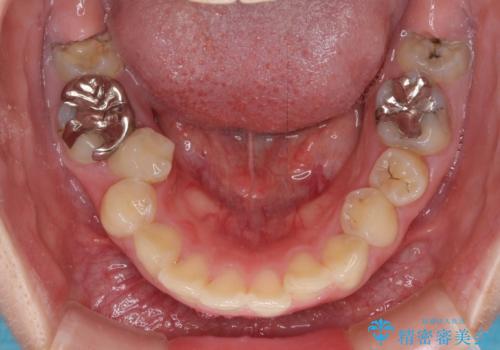

- 上の前歯の出っ歯とでこぼこの歯並びを気にして来院された患者様です。

上下顎歯列ともに前方に突出していましたが、上顎歯列がより前方位にあったため、上顎左右は第1小臼歯を、下顎左右は第二小臼歯を抜歯することとしました。

下顎は過剰歯が埋伏しており、それが原因となってスペースが閉じなかったため、途中で抜歯して速やかに仕上げました。